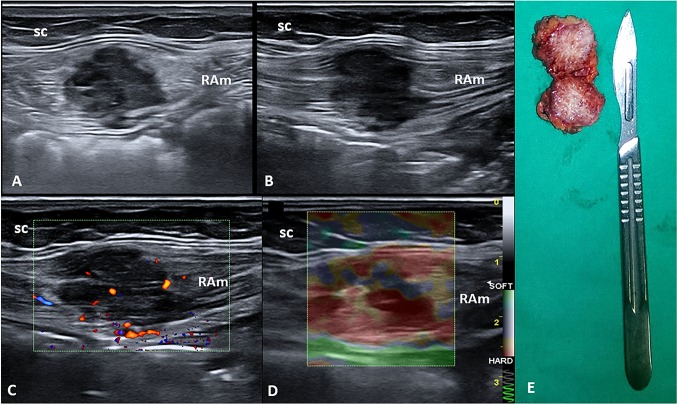

A 43-year-old woman was evaluated in our clinic complaining of pain over the hypogastric area. The obstetric history was characterized by multiple pregnancies with a cesarean section 3 years before. No previously diagnosed systemic disease was reported. The abdominal pain began two years after the last cesarean section, with a cyclic pattern strongly related to her menstrual cycle. During the physical examination, no abnormalities of the cesarean scar were detected and no palpable mass was identified. Ultrasound (US) imaging, using a multifrequency linear probe, showed a well-defined hypoechoic mass measuring 3 × 2.7 cm located on the right side of the Pfannenstiel scar and inside the rectus abdominis muscle (Fig. 2). Color Doppler modality revealed the presence of intralesional vascular spots, and strain elastosonography clearly showed a hard pattern compared to the surrounding tissues (Fig. 2).

Fig. 2.

Short (a) and long (b) axis B-mode ultrasound (US) images show the hypoechoic nodule located inside the rectus abdominis muscle (RAm). Fine intralesional vascular spots are depicted using the color-power Doppler mode (c), and a hard pattern of the mass is identified with the strain elastosonography modality (d). The macroscopic bilobed appearance of the corresponding surgical specimen after complete excision (e). sc subcutaneous tissue

Patients were referred for surgical treatment with complete excision of the masses (Figs. 1 and 2). The histological examination of the surgical specimens revealed benign endometrial glands and stromal tissues, thus confirming the diagnosis of endometriosis. Free surgical margins of 1 cm were histologically demonstrated in order to prevent local recurrence of the pathology. Note that the histopathological pattern also showed multiple widespread hemorrhagic foci inside the mass. The patients were discharged after uneventful hospital courses.

In our patients, transabdominal US allowed the identification of pathological masses not otherwise detectable with a normal physical examination. Also, tenderness in the site of the probe’s pressure and the location of the masses in relation to the surgical scar directed the diagnostic suspicion toward extrauterine endometriosis. Specifically, US examination showed hypoechoic masses with well-defined boundaries (benignity criterion), but with intralesional vascularization (malignancy criterion). Moreover, strain elastography produced a different echostructural pattern with respect to the surrounding tissue, thus confirming the ectopic nature of the masses.

Few previous works have investigated the role of elastography in endometriosis, and some authors have demonstrated that sonoelastography has high sensitivity and specificity for distinguishing endometrioma from hemorrhagic ovarian cysts [20]. Previously published papers have also evaluated elastography in diagnosing cesarean section scar endometrioma and have shown that the endometrioma presents a typical blue–green–red appearance with clearly defined outer borders (i.e., red and green areas correspond to the central hypoechoic soft areas) [21].

In our opinion, the two clinical cases demonstrate how a simple and repeatable method such as US allowed us to diagnose the abdominal wall masses that would not have been detected with a simple physical examination. Furthermore, the US study performed with a high-resolution linear probe allowed us to examine all the characteristics of the masses (structure, margins, ratios, and vascularization), avoiding the use of advanced imaging methods such as CT and magnetic resonance, which have known side effects [22]. The use of strain elastosonography allowed a qualitative estimate of the stiffness of the ectopic tissue. The main limitation of US, and of all imaging methods, is that the examination is not conclusive enough for a specific histopathological diagnosis. Therefore, since these US methods have the same diagnostic accuracy with lower cost and time requirements and fewer side effects, they seem to be the method of choice for the diagnosis of endometriotic pathology in the abdominal wall, in combination with an accurate past medical history (cyclic abdominal pain and specific pain localization next to the CS scar).